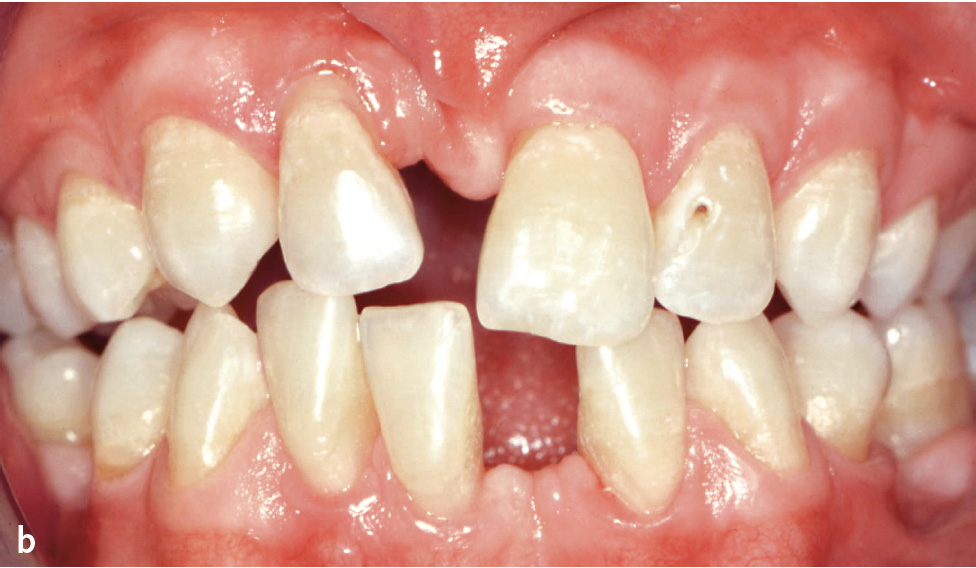

Die Gingivavergrößerung ähnelt klinisch und histologisch der hydantoininduzierten Wucherung und manifestiert sich am ausgeprägtesten im Bereich der labialen Papillen (Abb. 5). Die Veränderungen bilden sich nach Absetzen des Medikaments häufig wieder zurück. Durch eine regelmäßige Entfernung der Plaque ist es möglich, das Ausmaß der Wucherung deutlich zu reduzieren und oft auch vollständig zu eliminieren.

Abb. 5 Gingivawucherung bei Medikation mit einem Kalziumkanalblocker.